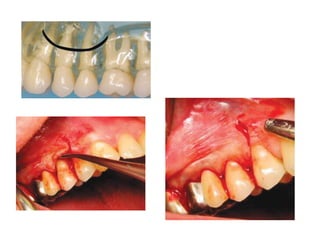

Tearing Mucosal Flap

Causes

Due to an inadequately sized flap which is

retracted beyond the tissue`s ability to

stretch.

As with a short envelope flap when the area

of surgery is at the apex.

Prevention

-Adequately sized flaps

-Gentle Retraction

Management

Reposition the flap & suture

If the tear is jagged, trim it before suturing